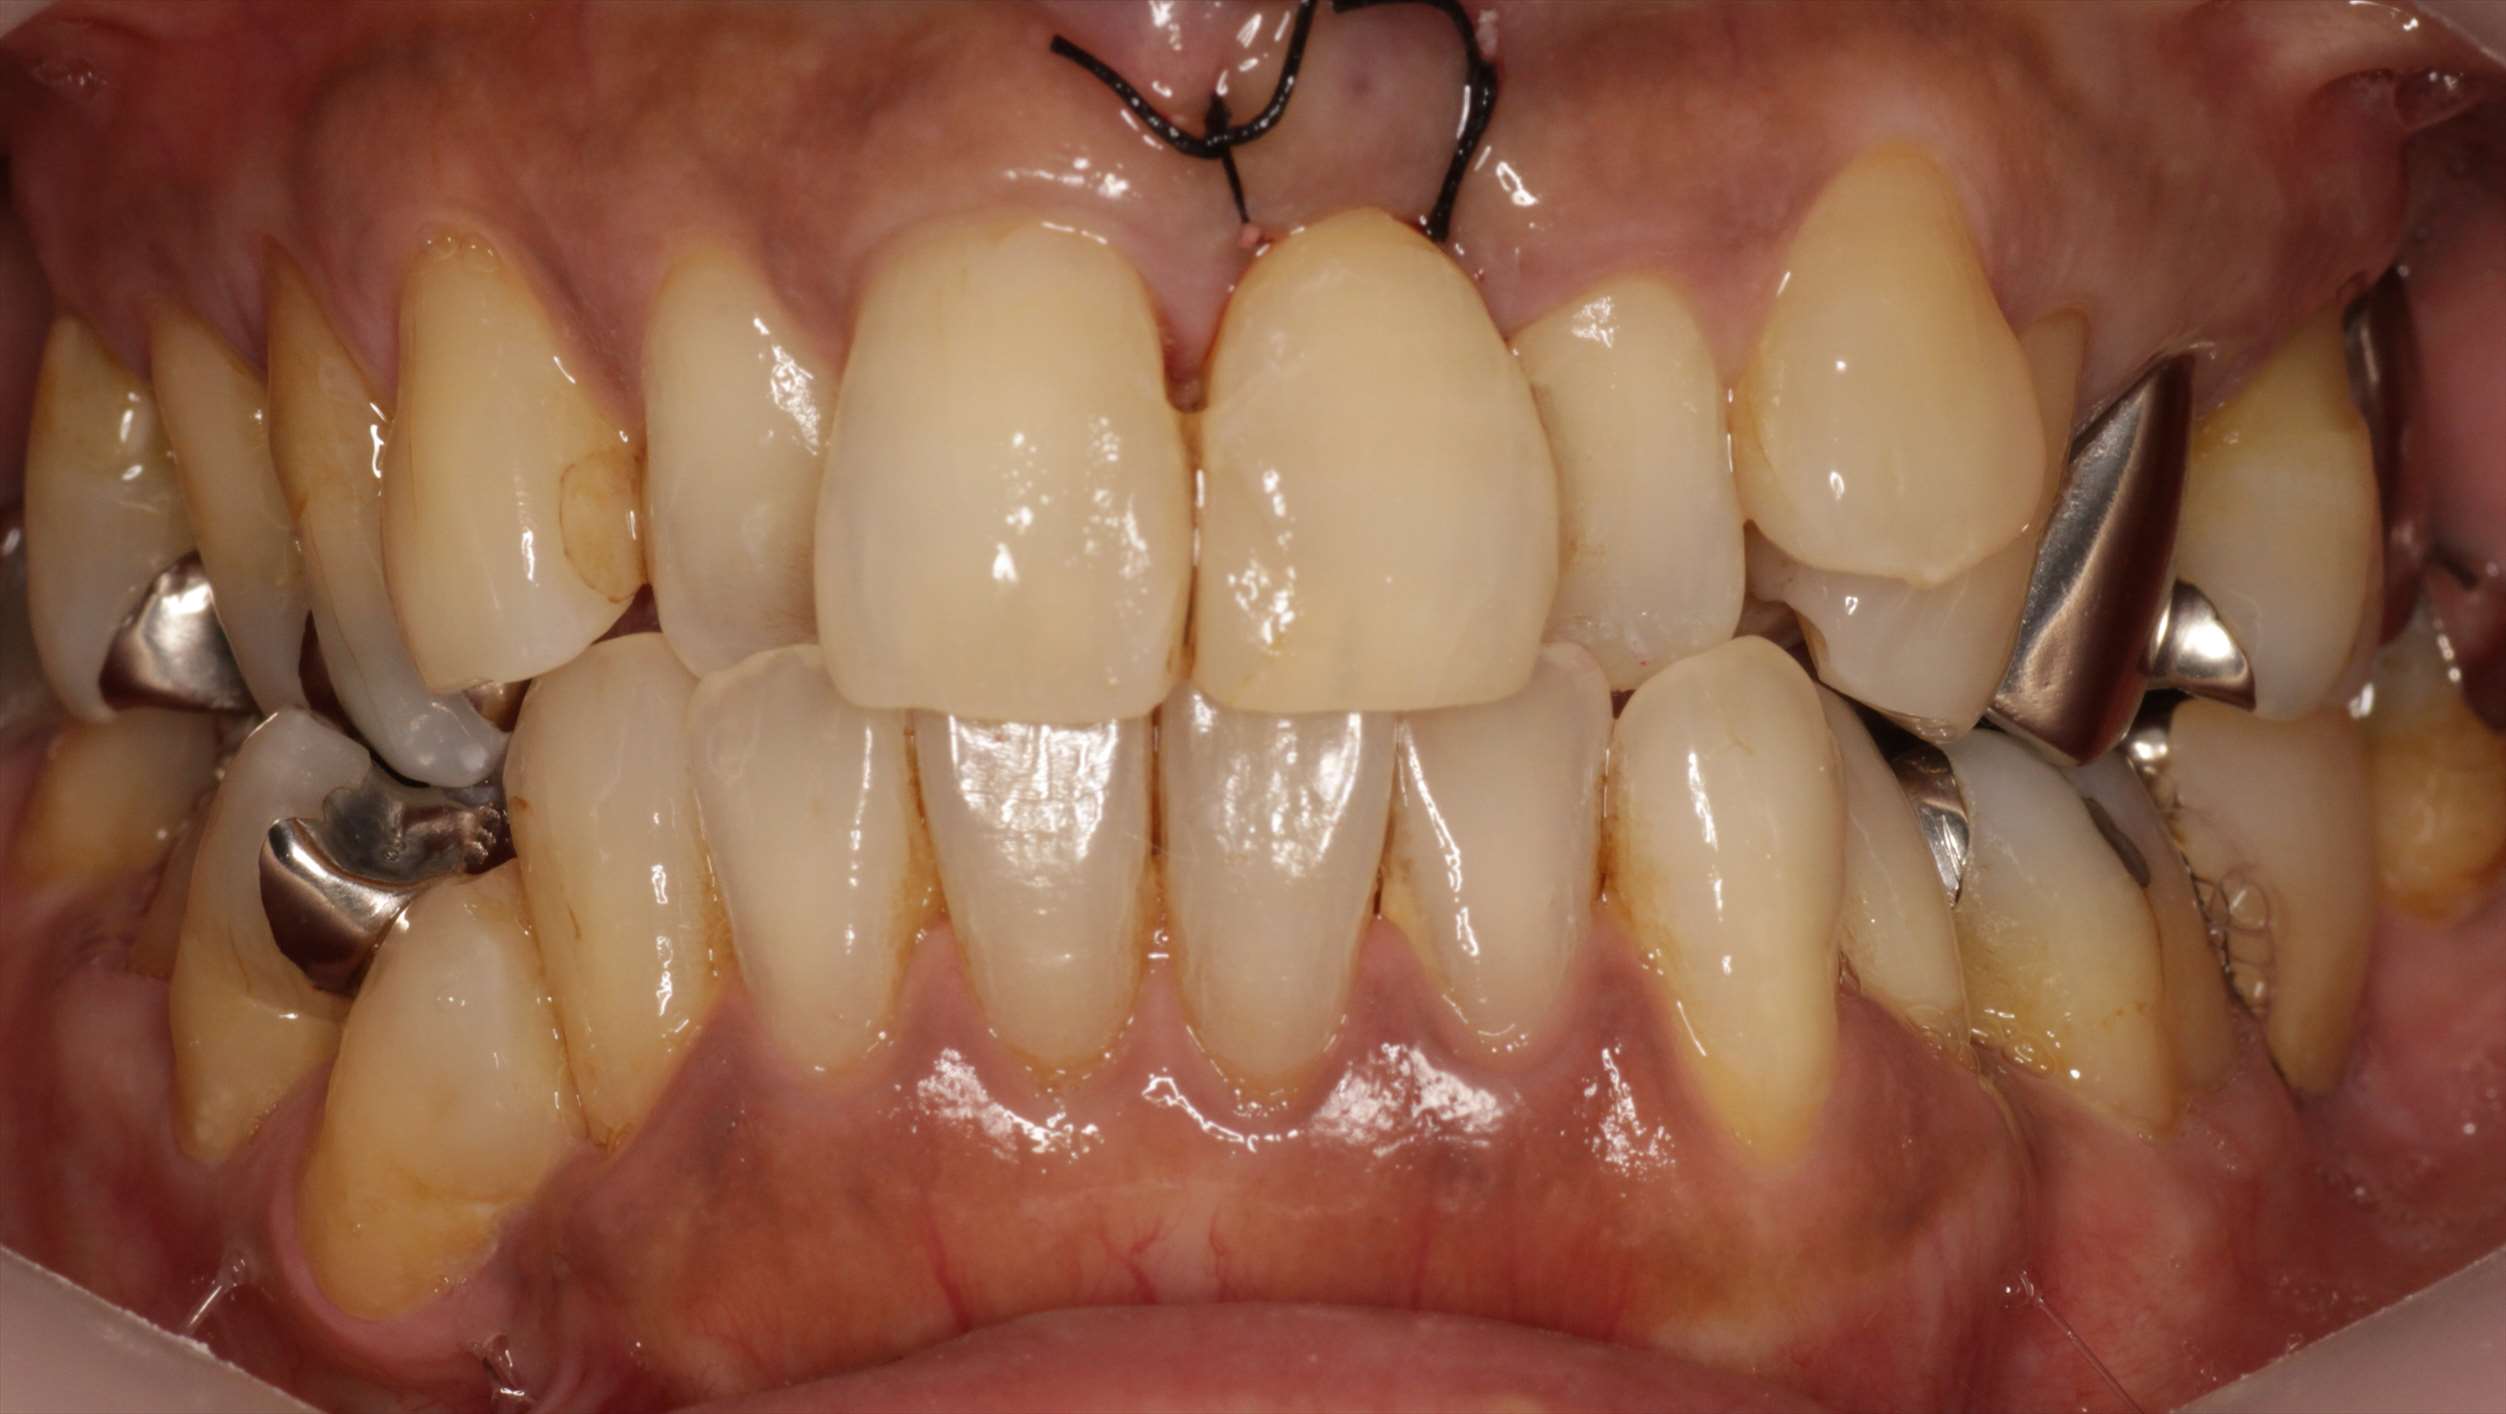

術後の側方面観です。